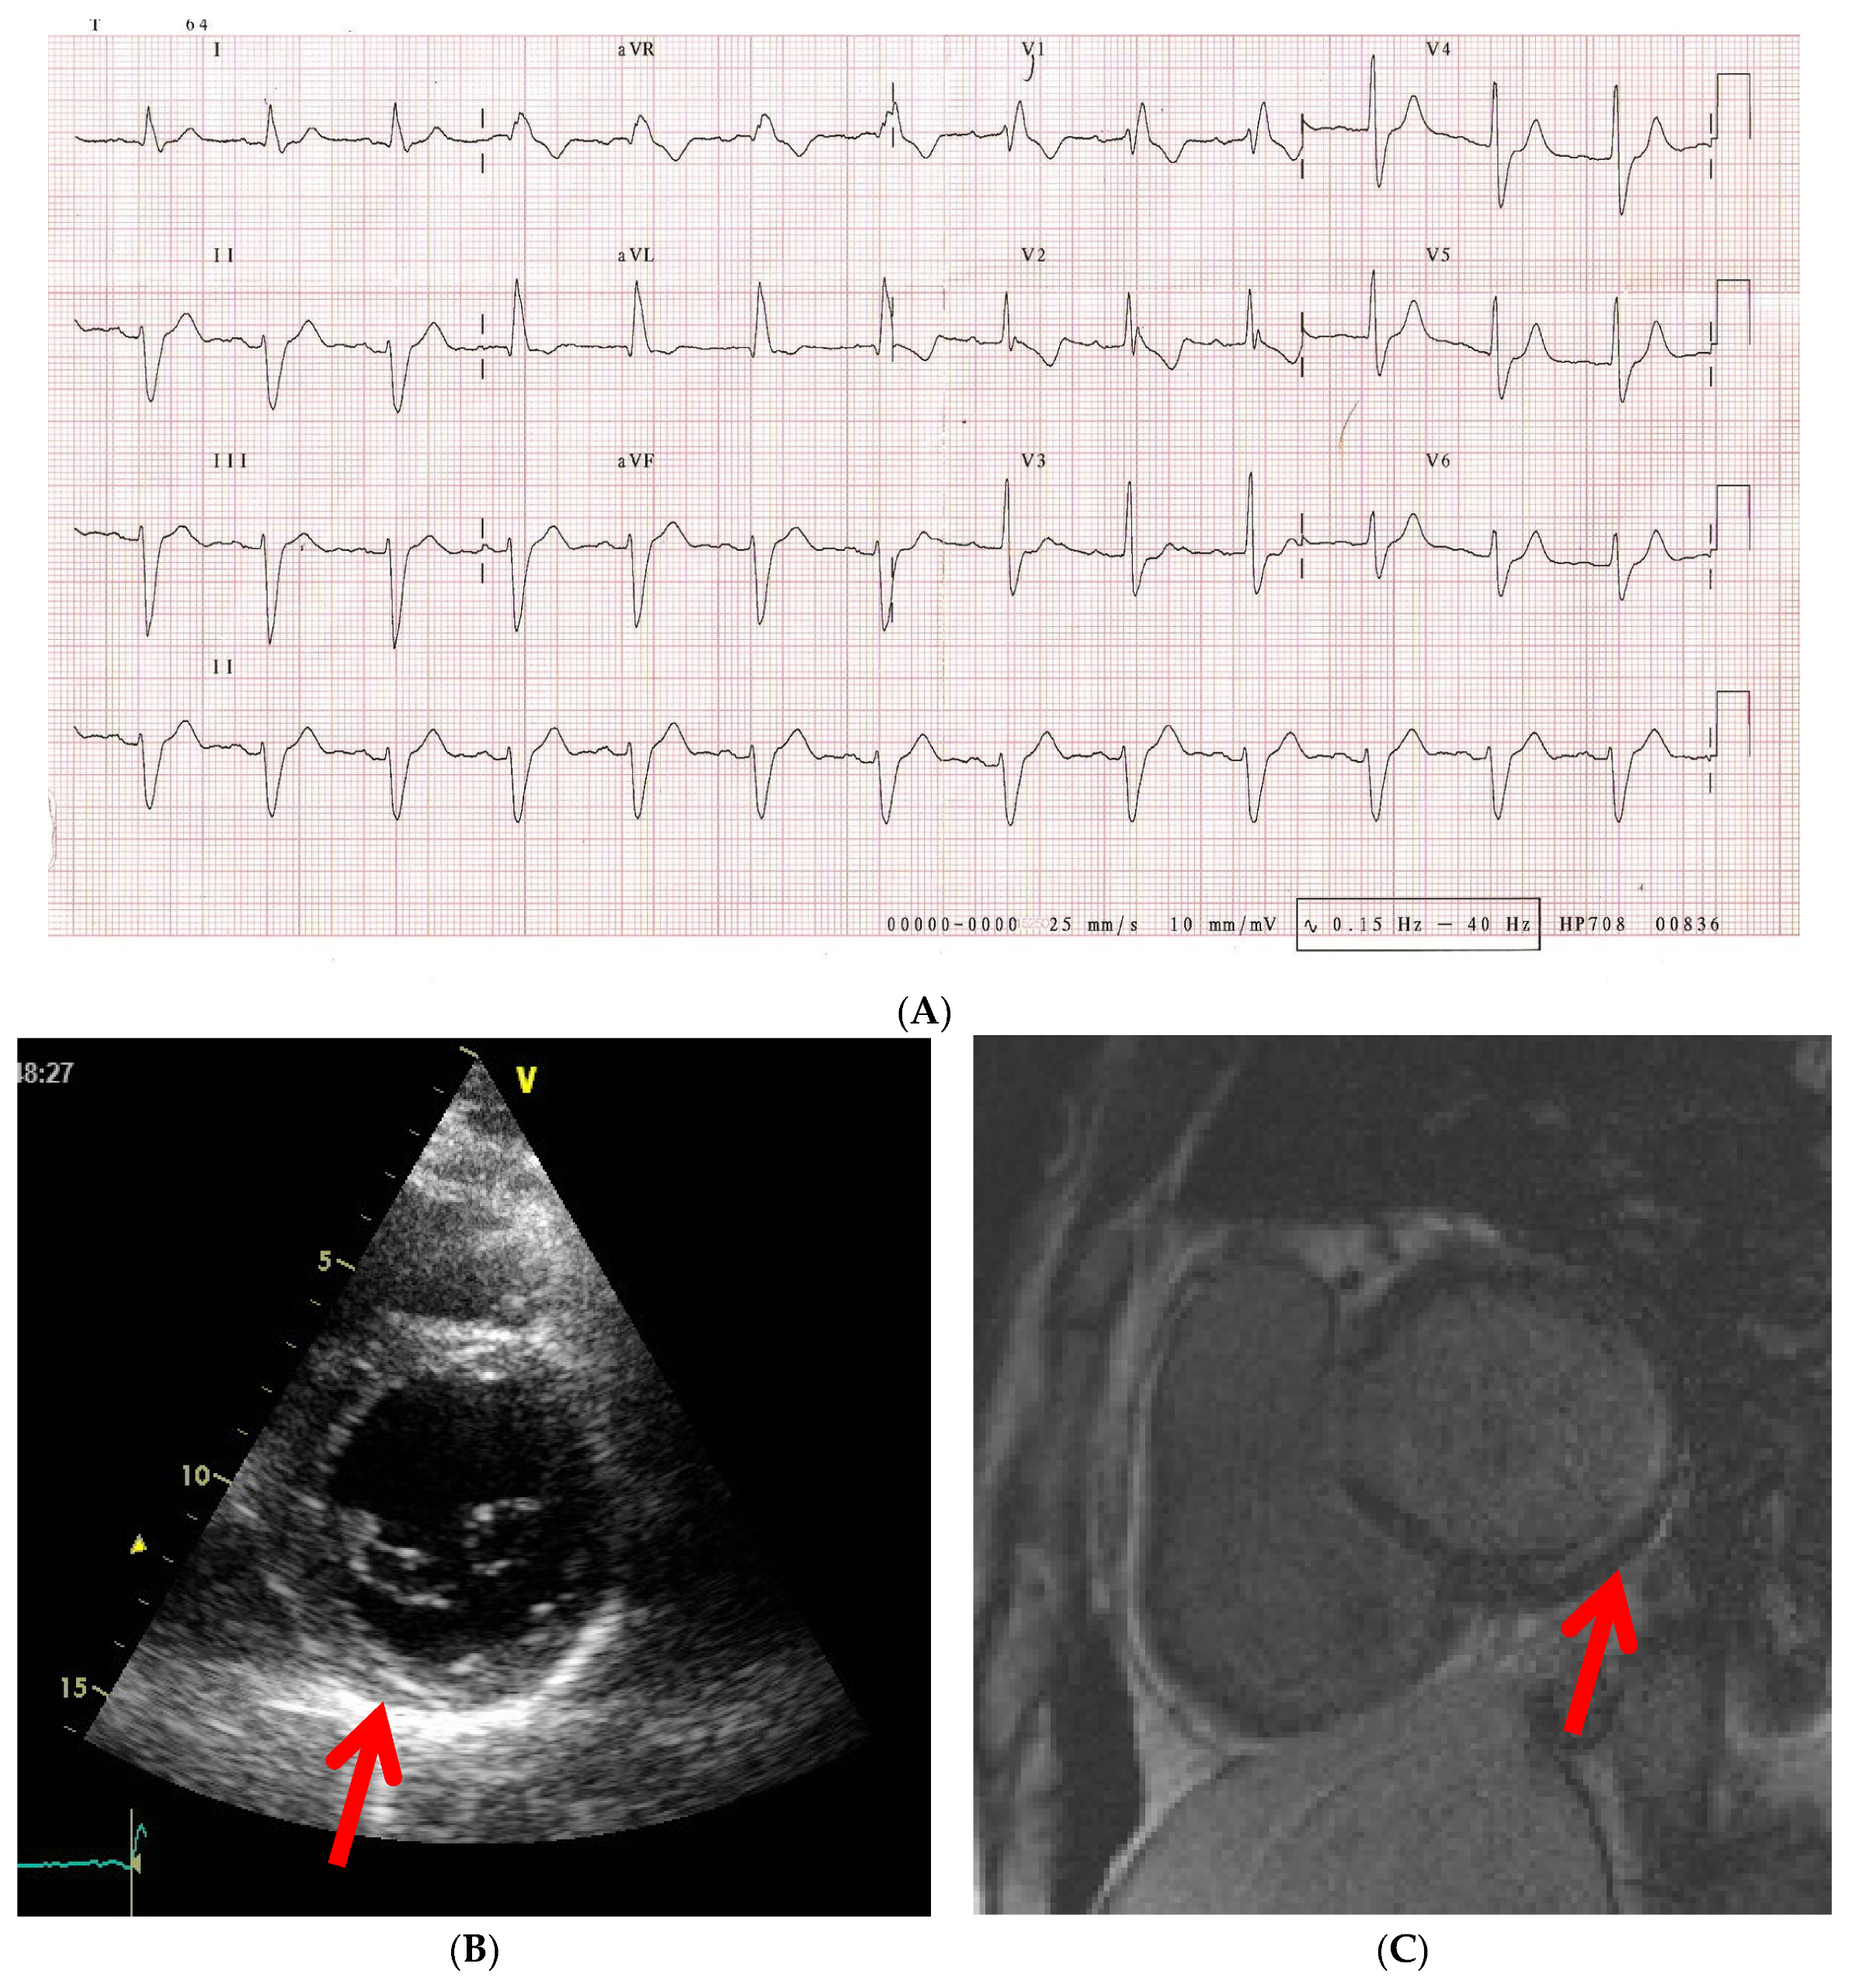

6.2. ECG Changes

| ECG | 25–75% SSc patients have abnormal tracings [39]. Independent predictor of mortality [39]. Anteroseptal myocardial infarction pattern—10% of cases [30]. High frequency of arrhythmias—especially ventricular events [47]. High frequency of PVB—correlates with mortality and SCD risk [48]; >1190 PVB/24 h—100% sensitivity and 83% specificity in predicting SCD or later necessity of ICD implantation [49]. Presence/severity of arrhythmias does not correlate with skin subtype/symptoms [39]. Arrhythmogeneity index—correlates with mRSS [50]. |